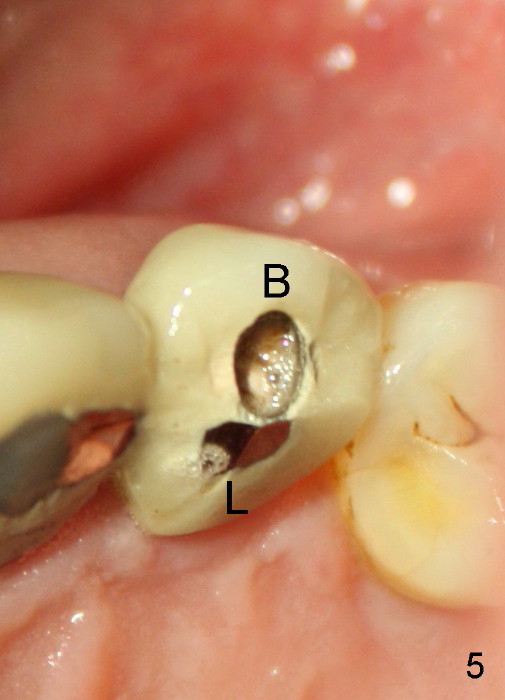

One month later, the fistula is regressing, while the pain reduces (Fig.4). It appears that the initial access is not extended lingually enough (Fig.5). The lingual canal is still non-negotiable when the access is enlarged (Fig.6). Working length of the buccal canal is confirmed with 30/.06 Gutta Percha in place (Fig.7). After explanation and consent, RCT is finished routinely. Two months postop, the buccal apical fistula resolves with no symptom (Fig.8). The retainer at the site of #12 is not removed to increase chance of finding the missing canal. It is part of a long bridge.